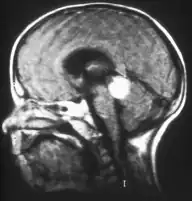

![]() Siatkówczak trójstronny w MRI głowy | |

Szyszyniak zarodkowy (łac. pineoblastoma, ang. pineoblastoma, pinealoblastoma) – rzadki, szybko rosnący nowotwór ośrodkowego układu nerwowego wywodzący się z niezróżnicowanych komórek szyszynki. Należy do grupy prymitywnych guzów neuroektodermalnych (PNET). Histologicznie należy do guzów drobnookrągłoniebieskokomórkowych i nie daje się praktycznie odróżnić od rdzeniaka. W patogenezie guza może mieć udział mutacja germinalna genu RB1, wywołująca obustronnego siatkówczaka; jako że szyszynka bywa określana "trzecim okiem", taka sytuacja kliniczna potrójnego guza określana jest jako siatkówczak trójstronny.